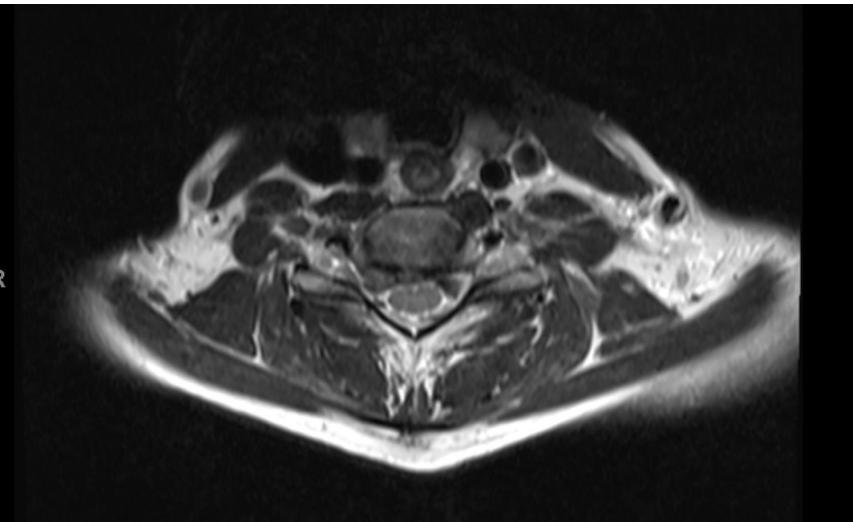

Imaging:

- MRI: Study of choice to evaluate degree of spinal cord and nerve root compression

Imaging Examples:

Surgical Treatment - Anterior Cervical Discectomy and Fusion: